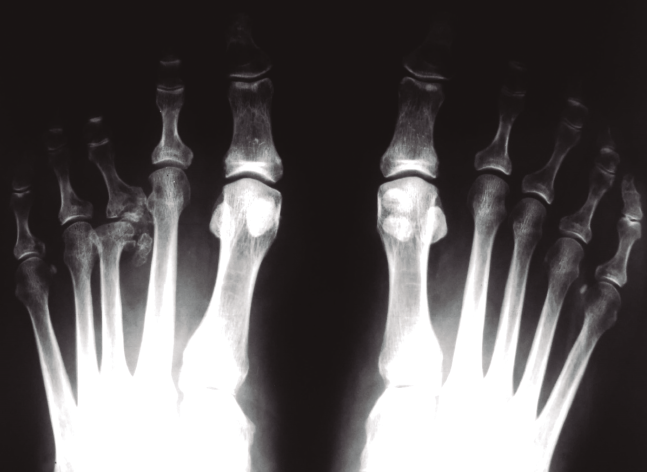

Figura 9. Esquema de la queilectomía. Resección de la corona osteofítica del metatarsiano y de la falange. Extirpación de cuerpos libres. Se asocian perforaciones anterógradas o retrógradas.

Figura 10. Queilectomía. Resultados a largo plazo. A: preoperación; B: postoperatorio inmediato; C: 17 años postoperación.

- Queilectomía y perforaciones: la queilectomía (Figuras 9 y 10) fue propuesta inicialmente por Freiberg. Consiste en realizar una sinovectomía, una remodelación amplia de la articulación con resección de la corona osteofítica, tanto a nivel del metatarsiano como de la falange, y la extirpación de los cuerpos libres articulares. Una vez realizada la limpieza articular, se procede, con una aguja de Kirschner, a las perforaciones, anterógradas o retrógradas en función del estado del cartílago. Con ello se pretende estimular la neoformación cartilaginosa y el remodelado articular. Con esta técnica se evitan acortamientos indeseados del metatarsiano y, por tanto, las metatarsalgias de transferencia, y se evitan también las reintervenciones motivadas por problemas con el sistema de fijación. Empleando esta técnica, que nosotros utilizamos habitualmente, también se han publicado buenos resultados(29,30,31) En nuestra revisión(13) sobre los resultados a largo plazo (seguimiento medio de 11 años) 13 pacientes se encontraban muy satisfechos y 3 satisfechos con el resultado de esta cirugía.